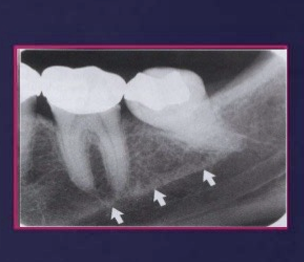

nutrient canals - often seen in patients with thin bone and in those with high blood pressure or advanced periodontitis

mental foramen

it appears as radiolucent, ill defined area between the apices of bicuspids - pre-molars

it represents the anterior terminates of the mandibular canals